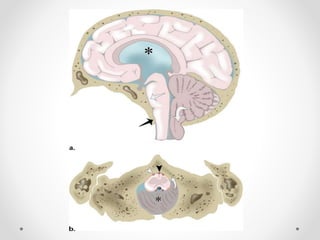

3. Thoát vị hạnh nhân

- Hạnh nhân tiểu não xuống thấp so với lỗ chẩm

=> Thân não hạ thấp, trung tâm hô hấp và tim mạch bị đè

ép vào bản dốc xương chẩm

- Nguyên nhân: giai đoạn sau của DTH, tăng áp lực hố

sau, chọc dò tuỷ sống dẫn lưu dịch não tuỷ...

CĐHA:

• Hạnh nhân tiểu não trở nên dẹt, nhọn, lồi xuống >3 mm

so với đường McRae line (tuỳ tác giả)

• Xoá bể lớn

• Ứ nước não thất do chèn vào não thất IV

• Nhồi máu tiểu não nếu chèn ép ĐM tiểu não sau dưới